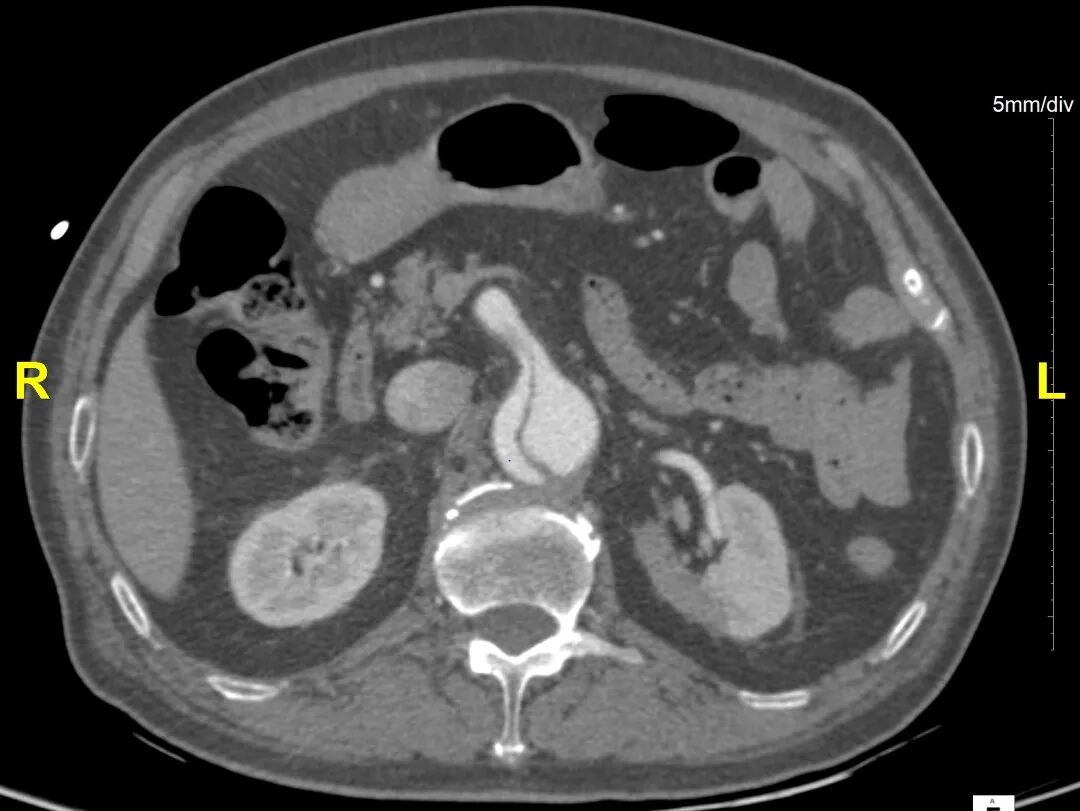

术后随访

术后随访复查,支架形态良好,真腔重塑良好,四分支及下肢血供良好。

横断面影像

3D影像